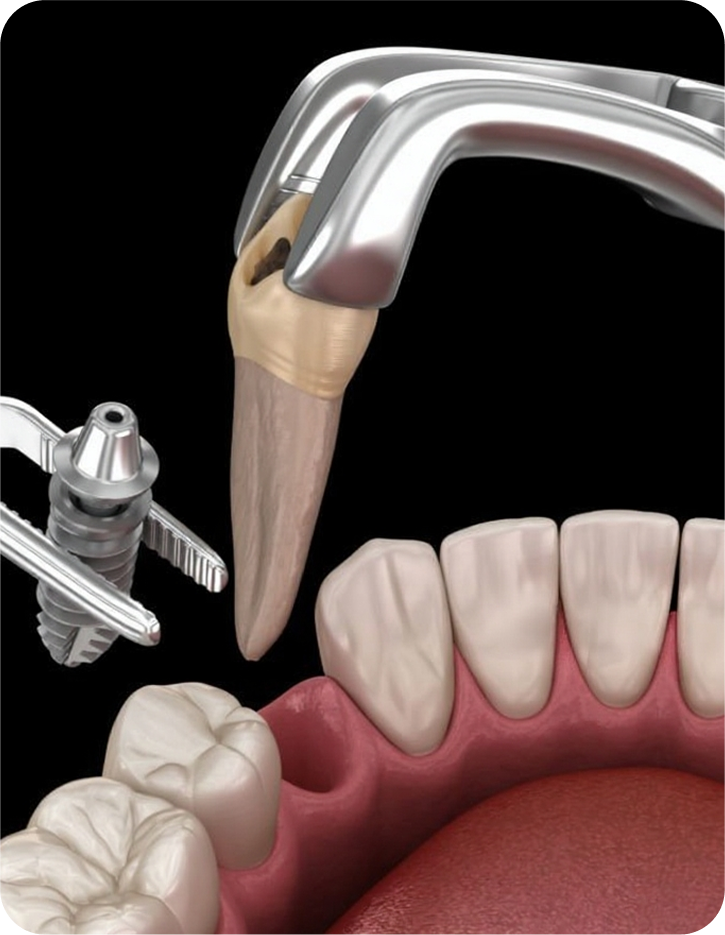

After a thorough clinical examination of your jaw bone, the Best dentist in Pune at Smilex confirms the available jaw bone by CBCT scan or X-rays. The doctors then administer a very small cut in the gums under local anesthesia. A painless drill sequence leads to the final drill position, after which the dental implants in Pune are placed in the bone. Gums are then placed back in their original position. A single implant procedure takes up to 45 mins to be done.

Immediate Implant

It is placed right after tooth extraction. It helps shorten the overall treatment time, reduce the number of surgeries, and preserve bone better.